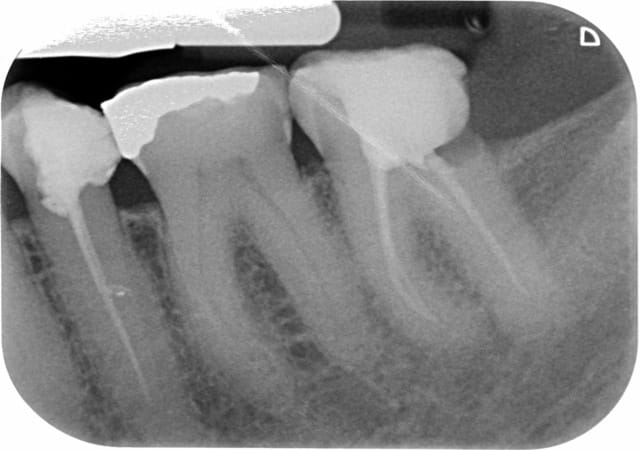

Une patiente de 71 ans, suivi depuis longtemps au cabinet par mon prédécesseur, se présente au cabinet pour une visite de contrôle. Je découvre en plus de 26 à extraire, une carie profonde en D de 37 ainsi qu'un traitement insuffisant sur 35. 35 et 37 devant être couronnées. Après ce 1er RDV, 2 rendez-vous sont pris pour réaliser d'abord le retraitement sur 35 puis l'endo sur 37.

Sachant qu'en plus le retraitement de 35 ainsi que le traitement de 37 ne va pas complètement à l'apex radiologiquement (mais avec le localisateur j'y suis).

L'obturation provisoire de la 47 n'a pas l'air étanche en distal.